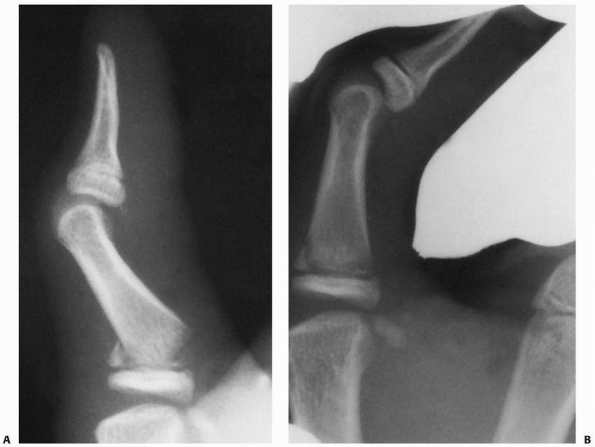

FIGURE 8-33 A. A 16-year-old girl with a severe intra-articular pilon fracture of the small finger PIP joint. B. Traction radiograph helps define fracture components. (continues)

|

![]() |

FIGURE 8-33 (continued) C. Dorsal exposure revealed ulnar condyle outside of joint requiring incision of extensor tendon for reduction. D. Reduction of joint surface and Kirschner-wire fixation. E. Postoperative anteroposterior radiograph shows restoration of articular surface. F. Lateral radiograph shows sagittal alignment of condyles. (Courtesy of Shriners Hospitals for Children, Philadelphia, PA.)